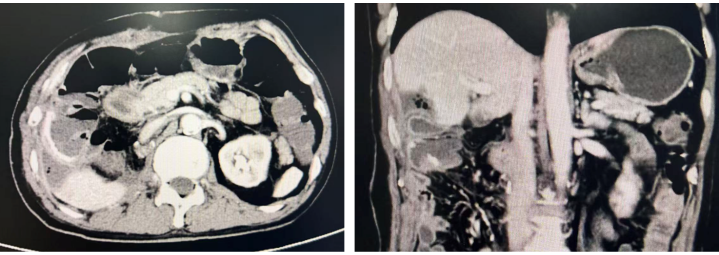

术前CT影像

肝胆胰外科二病区孙吉春教授接诊后指出,许先生的肿瘤复发进展速度很快,已经压迫甚至侵犯了肝脏、右肾、结肠、十二指肠乃至膈肌等周围器官,再次手术切除的难度和风险极大。面对这一复杂病例,医护团队迎难而上。为确保手术安全、提高治疗效果,科室启动了多学科诊疗(MDT)模式,联合放射科、泌尿外科、心胸外科、胃肠外科、麻醉科、手术室等多个科室专家进行深入讨论,再结合科室内组织的集体专家疑难病例讨论,最终制定了“先海扶刀治疗缓解肿瘤负荷并减轻疼痛症状,再尝试根治性手术”的治疗方案。